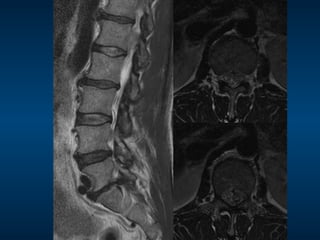

MRI: pre-vertebroplasty

STIR

2

3

T1 STIR